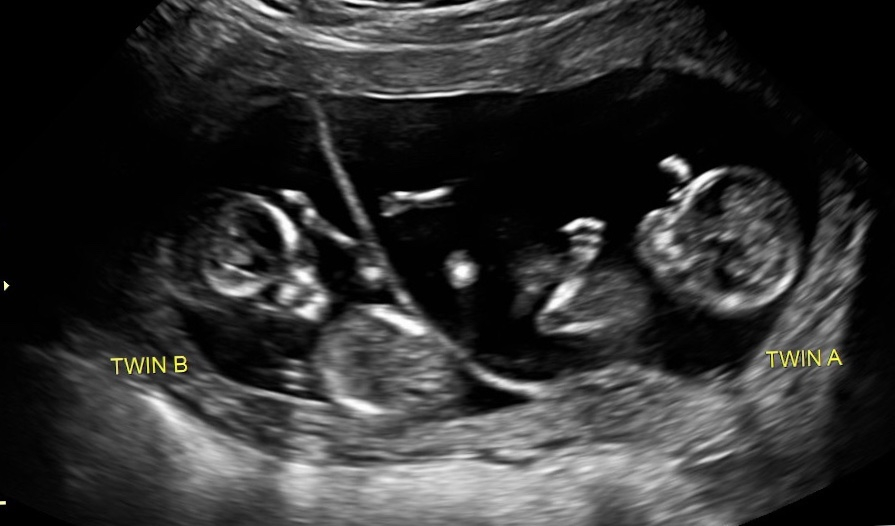

• We got one at 8 weeks. (Currently 11 weeks+4days) I didn't want to wait till later since my past history this year! My boyfriend,  6 year old daughter and me are so excited!